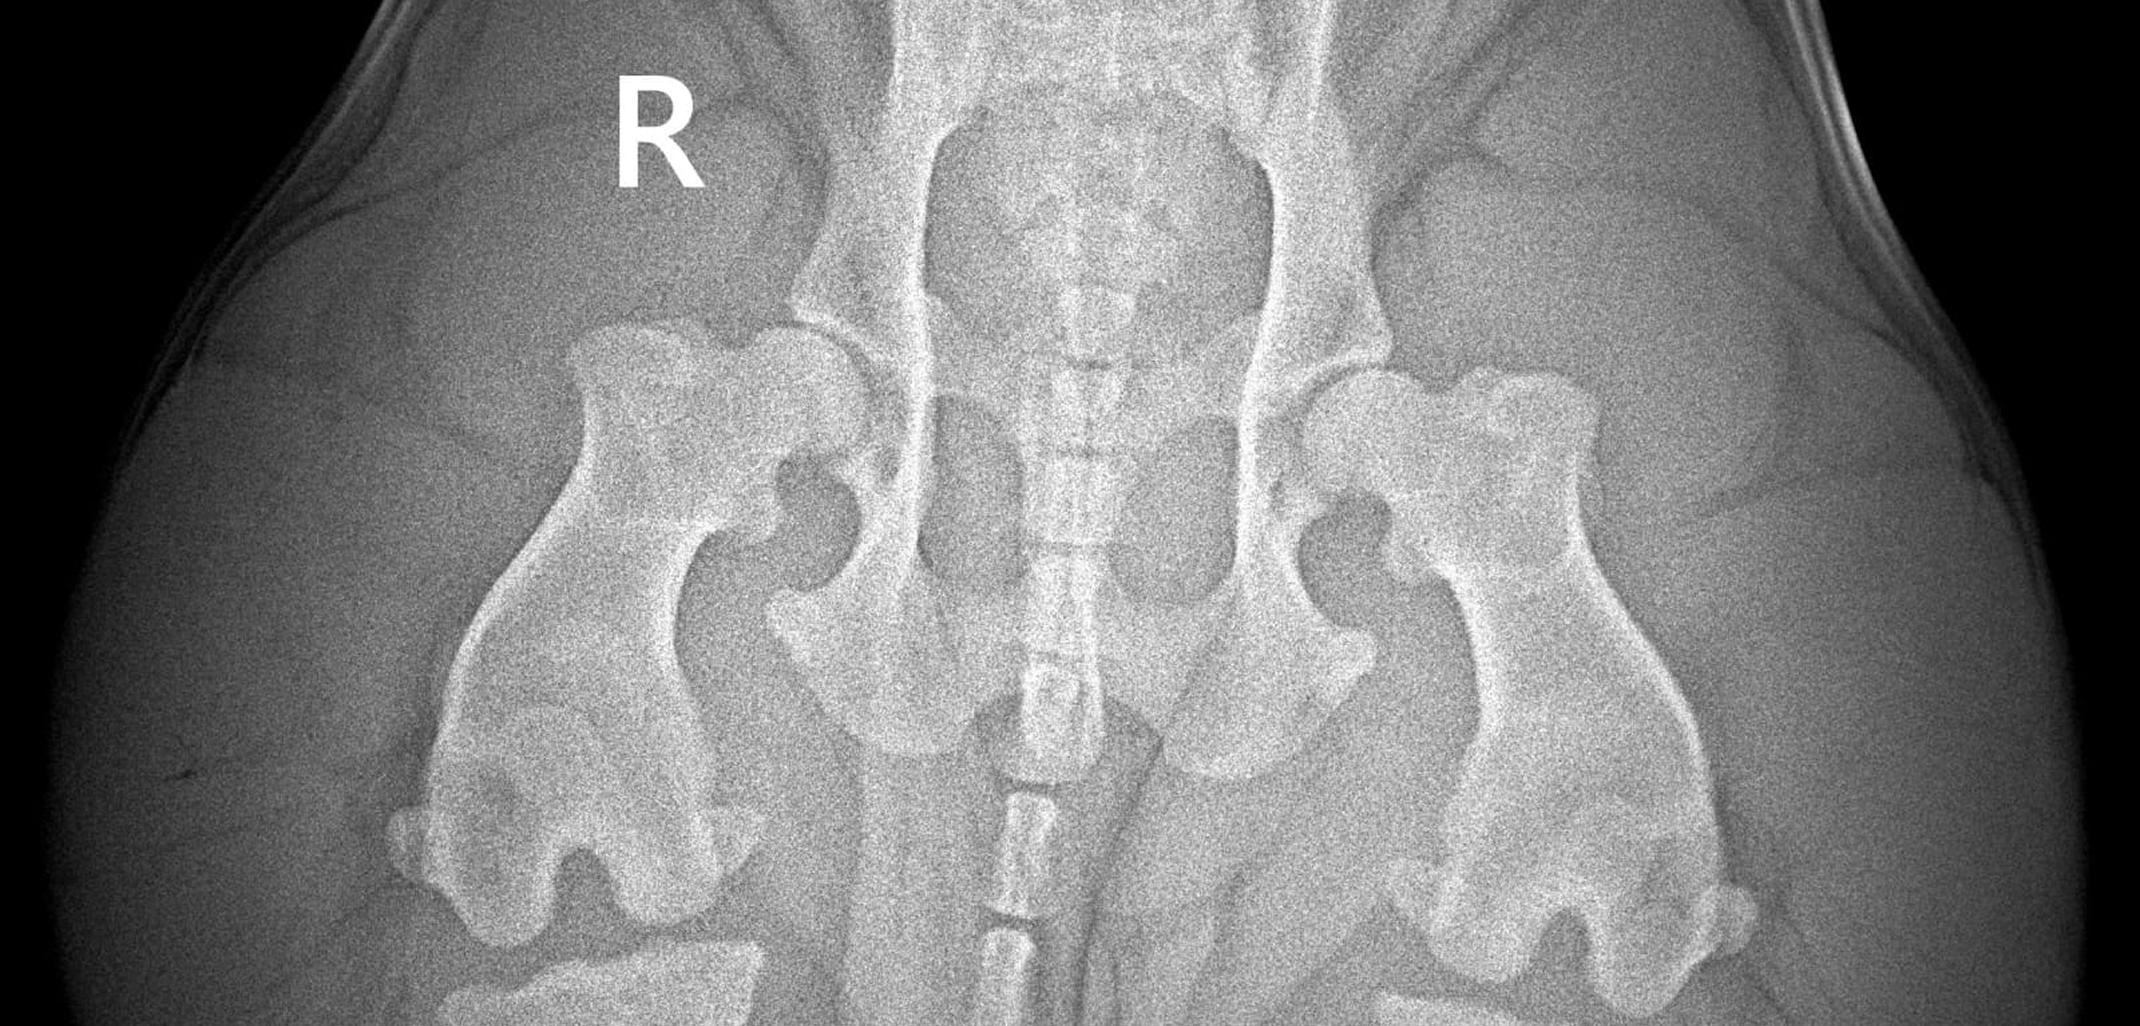

- эхокардиограмму сердца,

- осмотр ортопеда,

- УЗИ всех органов,

- вакцинации, чипирование, купирование ушей и обработки.